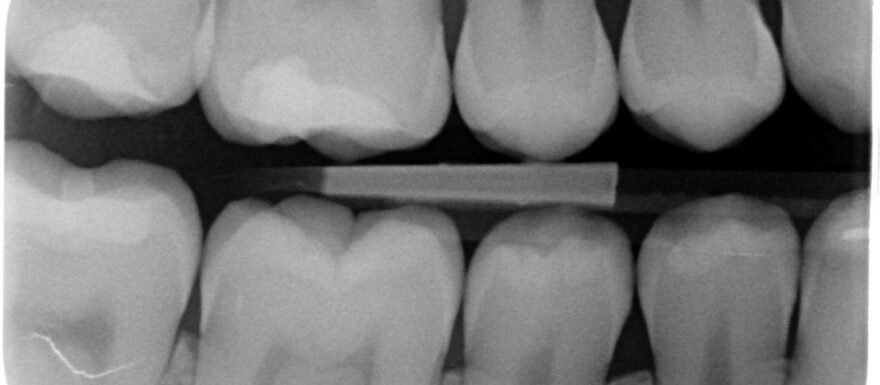

Röntgenfoto’s zijn van groot belang voor tandheelkundige diagnostiek. Tegelijkertijd brengt het gebruik van straling mogelijke gezondheidsrisico’s met zich mee. Daarom is het essentieel dat alle leden van het tandheelkundig team die met röntgenopnamen werken, beschikken over basiskennis van straling en weten hoe ze zich kunnen beschermen tegen schadelijke effecten.

• ken je het belang van de röntgendiagnostiek in de tandheelkunde